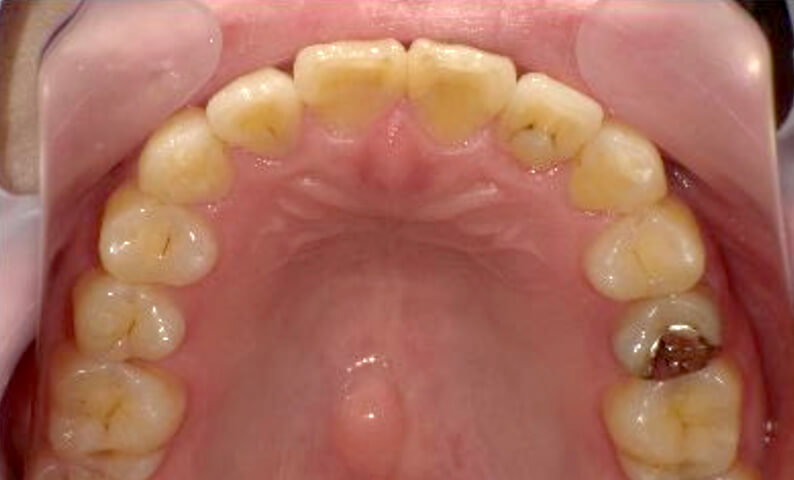

症例_029 上下顎の部分矯正

治療期間:12ヶ月金額:60万円+税女性出っ歯捻転歯前歯のガタガタ